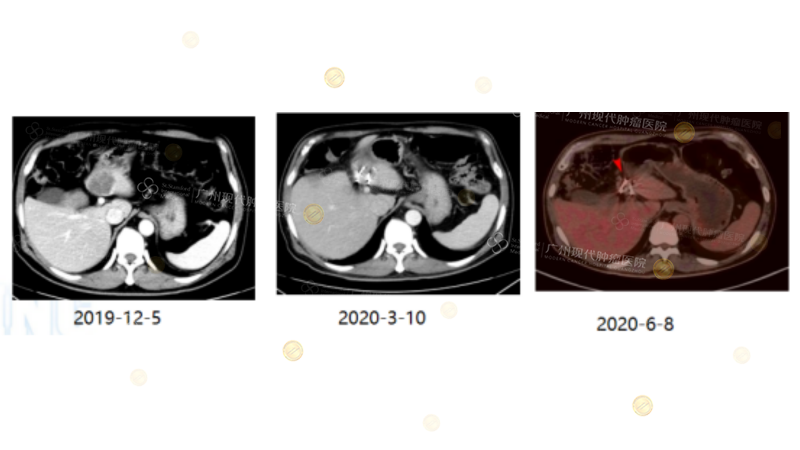

Case2

(Note: Rectal cancer patient from 2019. Lung metastases achieved CR after biotherapy. New liver metastases subsequently appeared. Considering secondary drug resistance, local Iodine-125 seed implantation was performed to aim for NED.)